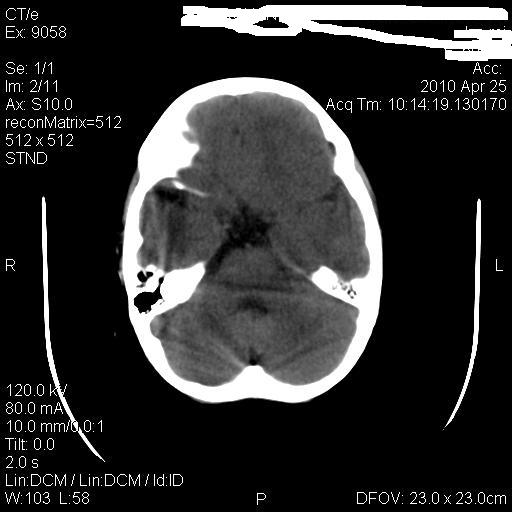

标题: PED3218:3岁女孩,曾有外伤史。未提供前片 [打印本页]

标题: PED3218:3岁女孩,曾有外伤史。未提供前片

发育略有障碍。欢迎大家发言。谢谢!

考虑右侧额顶叶脑软化灶并脑穿通畸形。

考虑:1)右侧额顶叶脑软化灶并脑穿通畸形。2)胼胝体发育不良。

右侧额顶叶脑软化灶并脑穿通畸形

支持考虑:1)右侧额顶叶脑软化灶并脑穿通畸形。2)胼胝体发育不良。

1)右侧额顶叶脑软化灶。2)胼胝体发育不良?

右侧顶叶软化灶并穿通畸形

考虑右侧额顶叶软化灶并脑穿通畸形,胼胝体发育不全。

还有脑室周围白质软化症